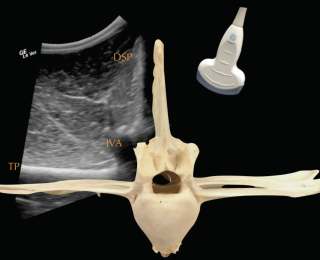

• Ultrasonography of the back should be combined with the radiographic examination and is particularly useful to examine superficial soft-tissue structures and the intervertebral articulations. To assess all structures of interest, both linear and convex transducers are required.

Deep to the ligament the fibrocartilaginous cap, visualised as a hypoechogenic line of approximately 1mm, is visible and runs parallel to the hyperechoic line of the DSP bone surface. The ISS cannot be assessed fully and a statement about potential iminging DSPs should not be made based on ultrasonography alone. The intervertebral articulations can be examined ultrasonographically, both in sagittal and frontal planes, using a convex transducer (Denoix 1999a; Reisinger and Stanek 2005).

The anatomy and ultrasonographic appearance of the joints change slightly from cranial to caudal. The mammillary process is more prominent in the thoracic spine and the joint is positioned further axial and closer to the DSP compared to the lumbar region. Signs of pathology in the intervertebral articulations (see Figure 4) include new bone formation and an enlarged outline of the facet (Denoix and Dyson 2003).